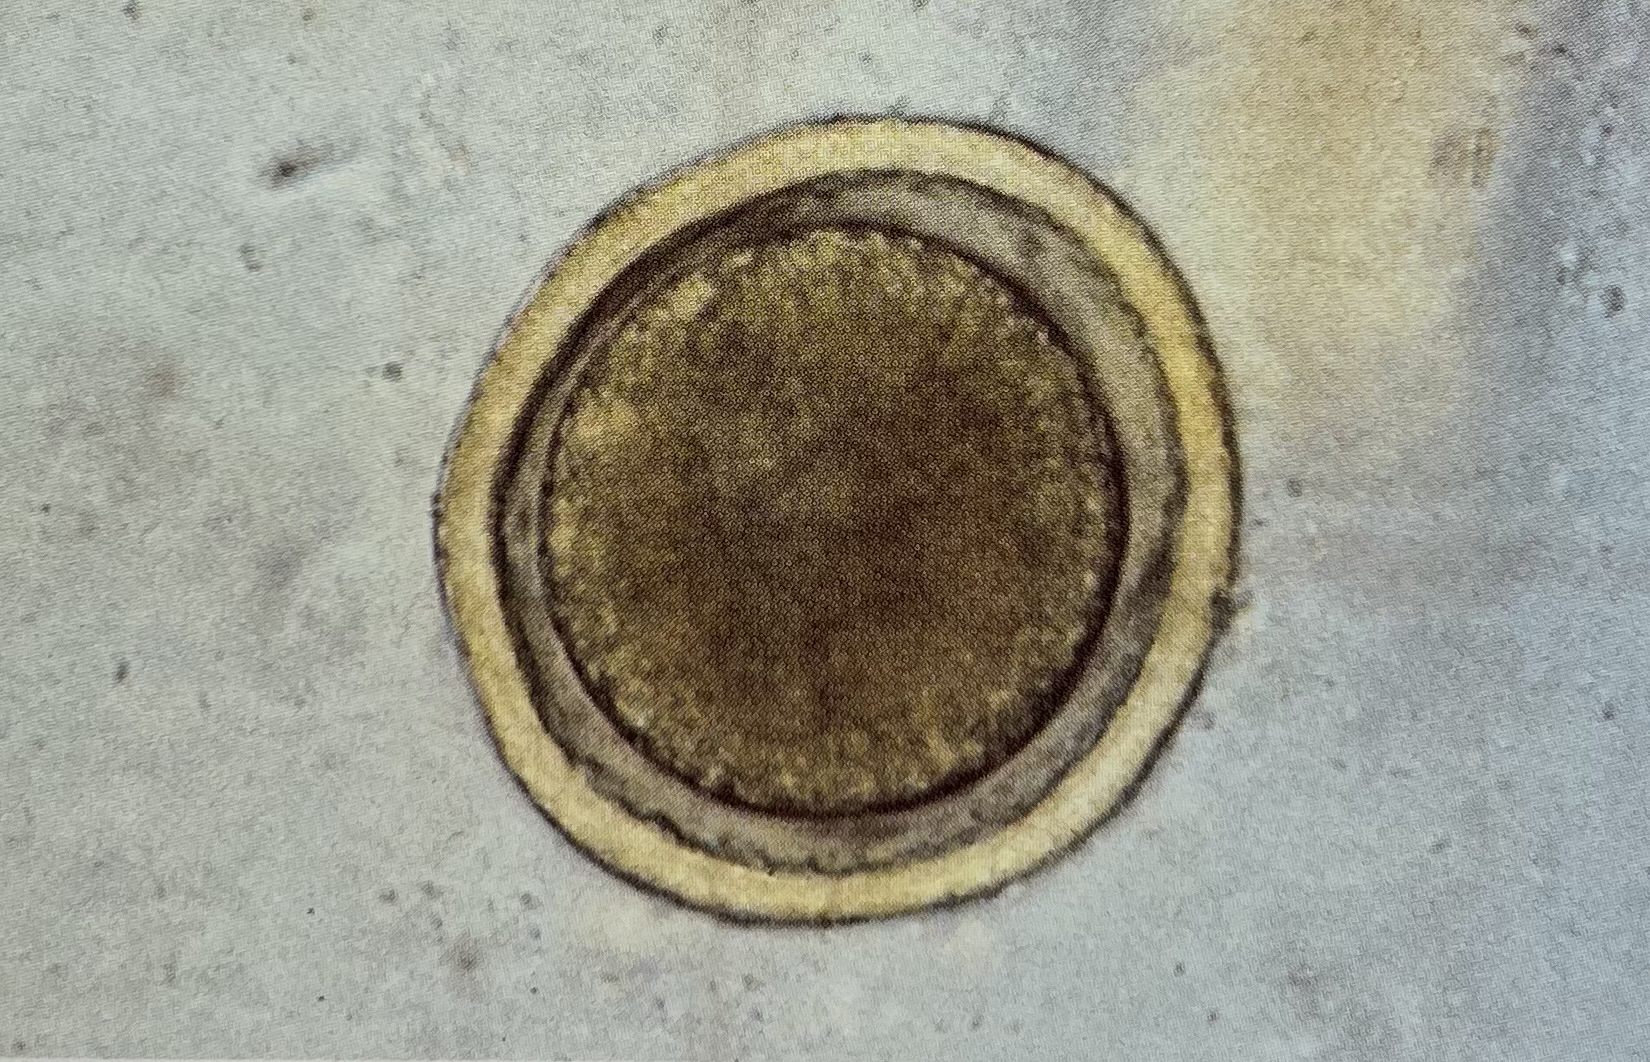

What egg is this? (Bigger: 75-90um)

toxocara canis

What egg is this? (notice the layers)

toxascaris leonina